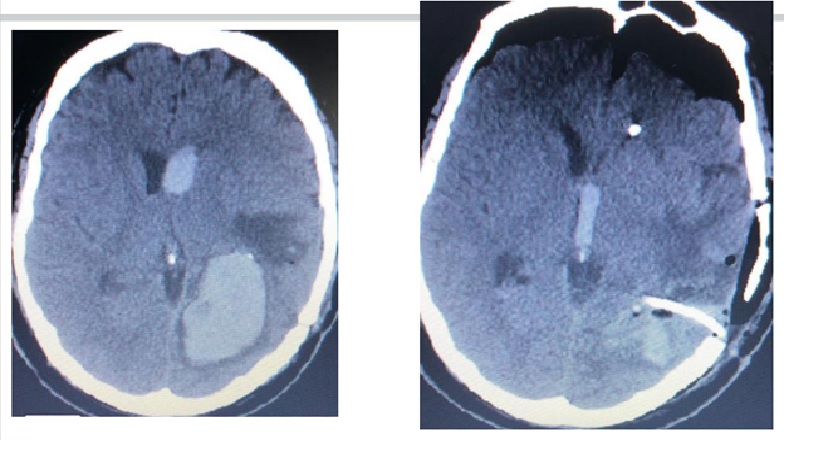

Không giống như xuất huyết não do chấn thương, đột quỵ xuất huyết không đáp ứng tốt với việc hút máu tụ bằng phẫu thuật. Tuy nhiên, nếu bệnh nhân có khối máu tụ lớn với khối lượng lớn và sắp xảy ra thoát vị, can thiệp phẫu thuật được chỉ định. Trong trường hợp chảy máu vào não thất, phải đặt ống dẫn lưu não thất để ngăn ngừa não úng thủy, đồng thời theo dõi áp lực nội sọ. Trong trường hợp chảy máu ở hố sau (thân não và tiểu não), thường phải phẫu thuật craniotomy vì nguy cơ chèn ép thân não và ngừng các chức năng hô hấp và tim mạch quan trọng.

Dấu hiệu đốm (spot sign) trên CTA (xuất huyết trong não)